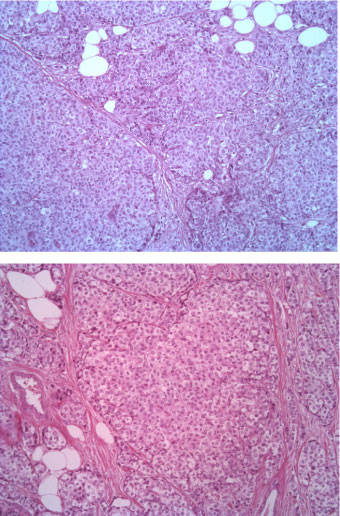

The tumor consists of densely cellular, solid nests (prevalent aspect in our case) and trabeculae of round cells of small-medium size, with abundant clear cytoplasm, separated by delicate fibrovascular stroma. The cells have round, regular nuclei and show some palizading arrangement at the periphery of the nests.

The immunophenotype was coherent with the diagnosis, showing bright positivity for synaptophysin, while CK5 and CK7 were negative.

Estrogenic and progestinic receptors showed diffuse positivity as well, with low proliferative fraction (Ki67/Mib1 < 5%) and no amplification of HER2 gene (data not shown) (Figure 1, Figure 2, Figure 3, Figure 4, Figure 5, Figure 6, Figure 7, Figure 8, Figure 9 and Figure 10).

Figure 1: EE ingrandimento 5X. View Figure 1

Figure 2: EE 10X. View Figure 2